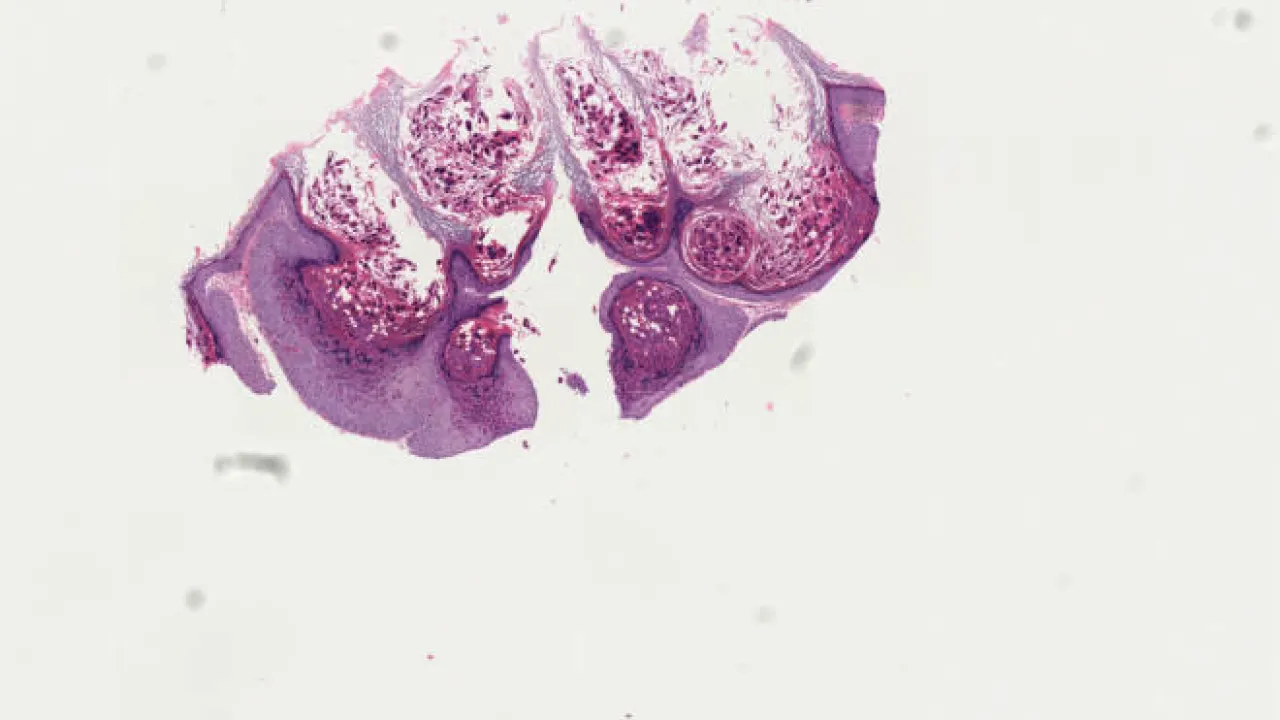

Lung, Pneumocystis jirovecii

Lung, Pneumocystis jirovecii pneumonia